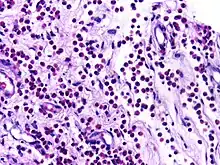

![]() | Dysgerminoma | Dysgerminoma characterized by uniform cells resembling primordial germ cells separated by fibrous septa with lymphocytes. | Category: Histopathology of ovarian dysgerminoma | Ovarian dysgerminoma |